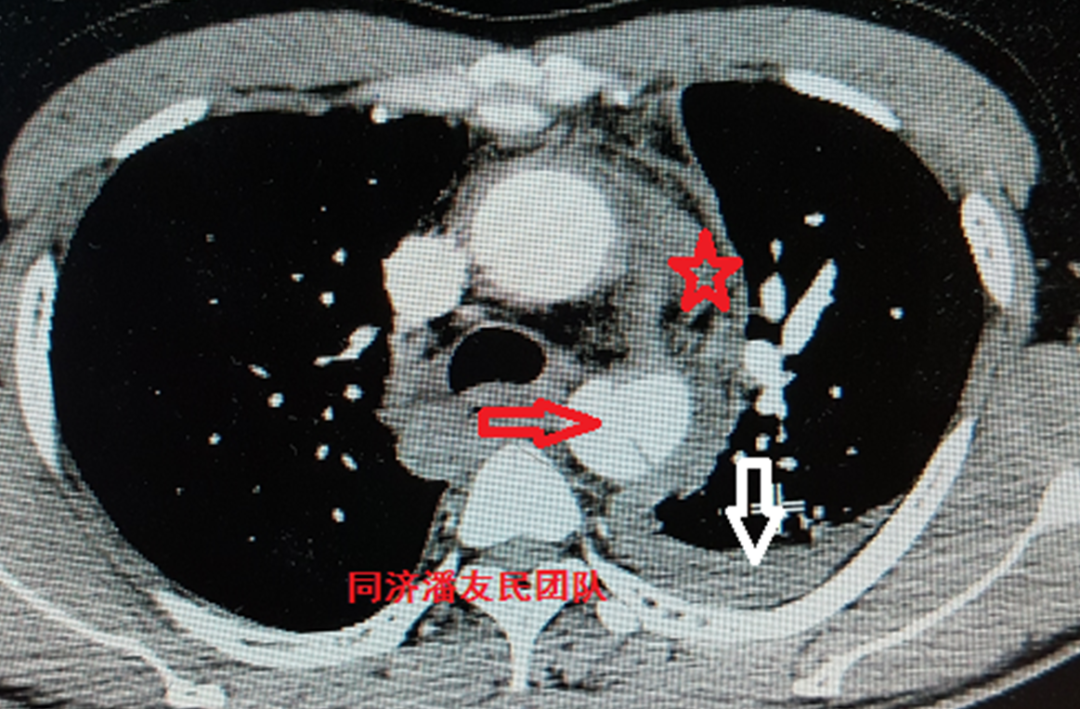

基层医院平扫CT提示胸降主动脉起始部内膜片影(图1),疑诊主动脉夹层(如何从平时CT发现主动脉夹层,请参考下文链接:没有CTA?这三招也能识别主动脉夹层!)。

图1:胸部平扫CT显示降主动脉管腔内可见内膜片(红箭头所示),考虑主动脉夹层。同时显示纵隔血肿(红星号)及左侧少量胸腔积液(白箭头所示)。